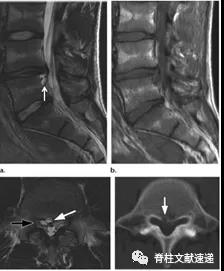

图注:背侧硬膜外椎间盘突出

图注:术前诊断倾向于硬膜外脓肿,术中见病灶呈致密纤维状,组织病理学检查显示纤维软骨盘伴反应性改变。